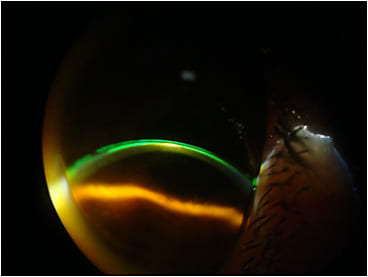

We refit the lens with a steeper central base curve and the same secondary base curve, which seemed to result in a good fit (Figure 1). But a few days later at the first post-new-fit follow-up visit, he still noted moderate discomfort. Re-evaluating the fit in a subsequent slit lamp examination, we observed that there was mild touch of the lens at the apex where the scar produced the small, rounded elevation (Figures 2 and 3).

His previous GP lens parameters were 58.50D x 45D base curves (BCs), –9.50D power, 9.6mm overall diameter (OAD), 6.5mm optical zone diameter (OZD), and 1.997 sagittal height (sag) (corrected for monovision in nondominant eye). We first changed the base curves to 59D x 45D (Figure 3), but it was not enough to clear the scar. The new lens that we designed had parameters of 60D x 46D BCs, –12.50D, 9.8mm OAD, 6.8mm OZD, and 2.187 sag, with a slighter increase in the optical zone (Figure 4). We decided, with the patient, to improve his distance vision, and he is still able to read J2 without reading glasses.

This case demonstrates an interesting aspect in recent corneal GP fitting that we have done. In some specific cases, we are utilizing the sag value for corneal GP fitting. This is the same concept used in customizing scleral lens fitting—adapting the different zones and curvatures in a way to obtain the best possible alignment to the ocular surface. Here, we augmented the sag utilizing a combination of a steeper central base, a steeper secondary base curve, and also a slight increase in the central optical zone. This induced greater pooling and was steep enough to vault the elevation obstacle while preventing the formation of microbubbles. Visual acuity was not affected due to the greater pooling of the steeper lens.

Working with sag values in corneal GPs is similar to working with them in scleral lenses, but it is important to understand that the magnitude of the change in microns is significantly smaller compared to with scleral lens fitting. Be sure to examine the fitting using all resources, especially slit lamp observation with fluorescein and cobalt blue illumination, both frontal and at 45º with a thin slit light. I strongly recommend capturing these images for posterior examination on a large screen. This way, you can take the time needed to plan the changes that you believe will result in the desirable effect. Remember that challenging cases frequently need one or more attempts to acquire the best possible fitting. We usually charge a higher fee in these cases, always making sure that the patients understand the difficulty of the case.